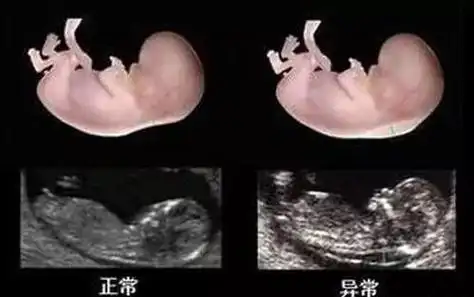

孕12周nt暗示男女(孕12周nt暗示男女知乎)